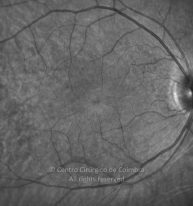

Paciente de 37 años con traumatismo contundente y ruptura del globo ocular. Presenta ruptura esclero-uveal, hifema, hemovítreo, desgarro periférico y temporal de la retina, hemorragias subretinianas y múltiples desprendimientos serosos.

MAVC: 20/25 OD, nueve años después de las cirugías (sutura escleral de la desinserción del músculo recto externo, vitrectomía posterior y fotocoagulación láser en el borde del desgarro retiniano, desprendimiento de retina inferior con proliferación vitreorretiniana y líquido subretiniano con algo de sangre; peeling de la membrana epirretiniana y maculorrexis de la MLI).